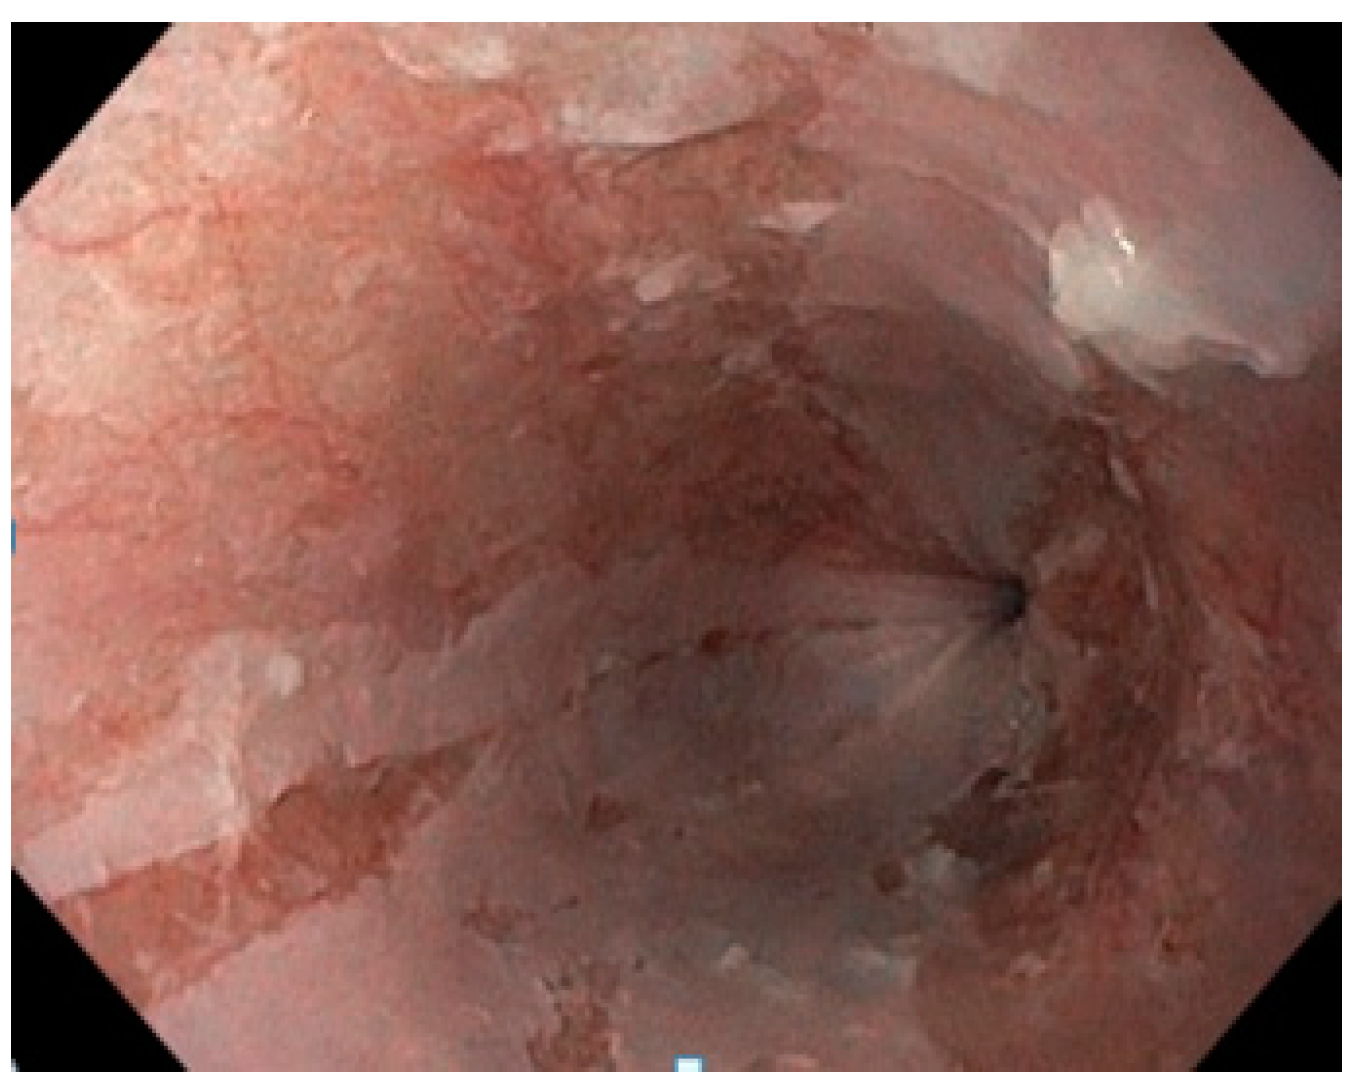

She underwent an upper GI endoscopy which revealed pinkish longitudinal mucosal strips adhering to the middle and lower esophagus, with mucosal erosions observed following detachment, and normal looking mucosa between the lesions. The endoscopic appearance of the esophageal casts, also known as gift-wrap ribbons or wrap paper, was suggestive of EDS or sloughing esophagitis (Figure 1). The stomach mucosa appeared to be normal.

Figure 1.

Endoscopic findings showing the esophageal mucosa with longitudinal strips from the sloughing of the mucosa with a “gift-wrap ribbons” or “crepe-paper” appearance.